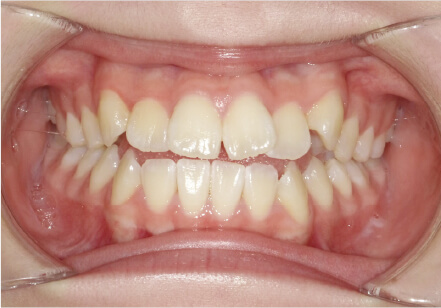

叢生の症例

41歳

/

女性

相談内容

横から見た時のガタガタが気になる

カウンセリング・診断結果

インビザライン、正中は上11に合わせていく、抜歯・拡大装置・IPR・アタッチメントOK

治療内容・方法

アライナー矯正

術後の経過・現在の様子

クリアライナー使用

治療のリスク

痛み・歯根吸収・歯肉退縮・虫歯・後戻り

費用・治療期間

880,000円、7ヶ月

トレーニングなど